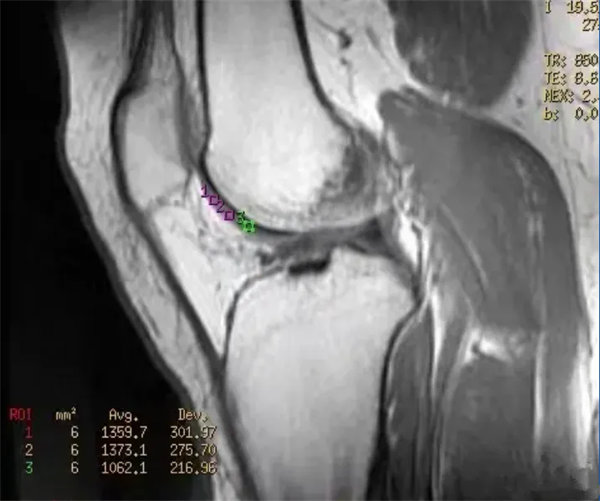

图5

原始图,损伤软骨T2mapping成像

图6

定量图,损伤软骨T2mapping成像,测相应软骨T2值。感兴趣区(ROI)5、6、7点位软骨T2值增高,分别是52ms,52ms,48ms。